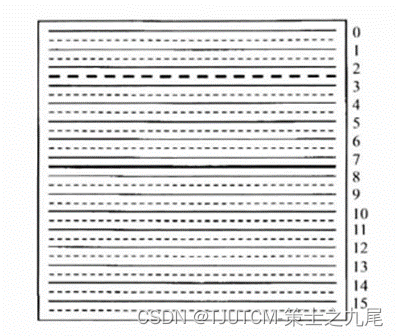

以K空间测量行和附近缺失行构成一块(block)的话,AUTO-SMASH只有K空间中心一块的采样是满足奈奎斯特判据的,而(变密度)VD-AUTO-SMASH则在K空间中央区域有不止一块的采样时满足奈奎斯特判据。

实线表示测量的K空间行,小点线表示缺失的K空间行,在中间区域额外测量的奈奎斯特采样行(大点线)即ACS行用来确定合成缺失行(小点线)的权重因子,相位编码在竖直方向

((a)R=2,(b)R=3,©R=4)